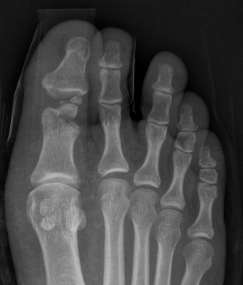

Great toe MTPJ dislocation

Pathology

Hyperdorsiflexion

Metatarsal head dislocates plantar

- tear of plantar plate / disruption bipartite sesamoid

- may buttonhole through capsule / plantar plate

Xray